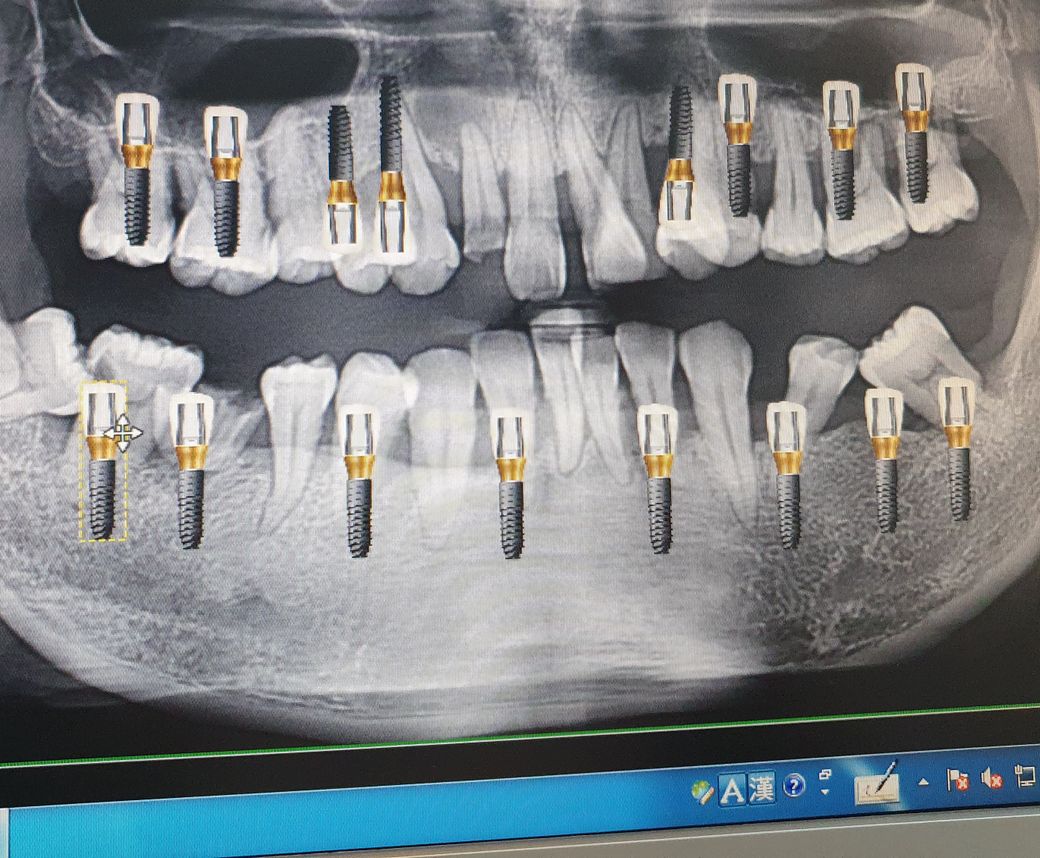

임플란트 16개를 해야한다고합니다 ㅠㅠ

• 1번 째 사진

잇몸의 상태가 안좋아 다수의 발치와 임플란트가 필요해 보입니다.